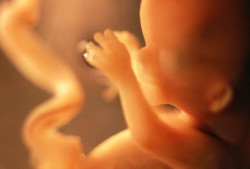

Los científicos crean un modelo de un embrión humano temprano a partir de células de la piel

Un equipo internacional de científicos dirigido por la Universidad de Monash, en Australia, ha generado un modelo de un embrión humano a partir de células de la piel, en lo que supone un descubrimiento que revolucionará la investigación sobre las causas del aborto espontáneo temprano, la infertilidad y el estudio del desarrollo humano en sus primeras fases, según publican sus autores en la revista `Nature`.